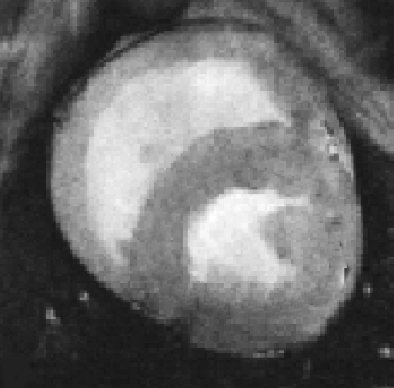

This FE approach can be easily adapted to other images, for example in Fig. 6 left, we apply this approach for segmenting a ventricle MRI heart image, taken from Angenent2006 with permission from1. In the center of Fig. 6, the FE mesh is shown and on the right of the figure, we see the segmentation of the adaptive eigenspace using FE. As discussed in Rem. 1, we do not always get a binary segmentation, but this is easy to get using a standard threshold.